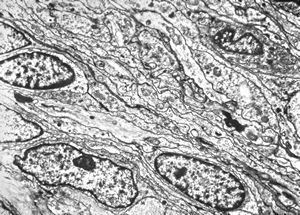

F,23y. | - n.suralis- hypertrophic demyelinizing neuropathy (onion bulbs)